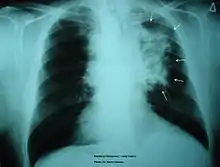

A patient's lung diagnosed with lung cancer